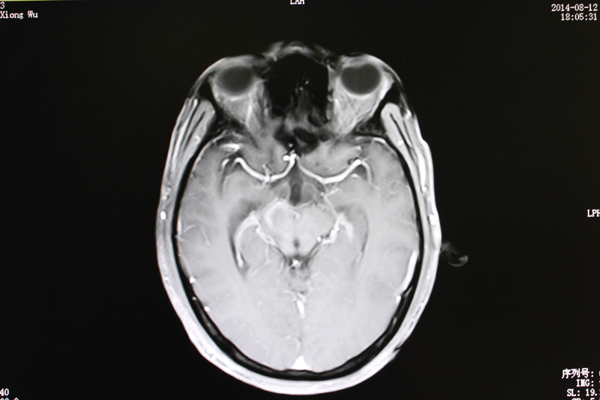

8月12日,从最新的MRI检查结果上显示,病灶水肿范围较之治疗前明显缩小。

主管医生姜盛强介绍肿瘤治疗效果的标准:“有五个层面,包括恶化(肿瘤继续增大);无变化(肿瘤缩小在25%以下);微效(肿瘤缩小在25%-50%之间);有效(肿瘤缩小在一半以上);显效(肿瘤病灶消失)几个等级。”

“黄先生属于有效,也就是从肿瘤已经明显缩小,肿瘤对脑部神经和组织的压力减小。”

治疗后